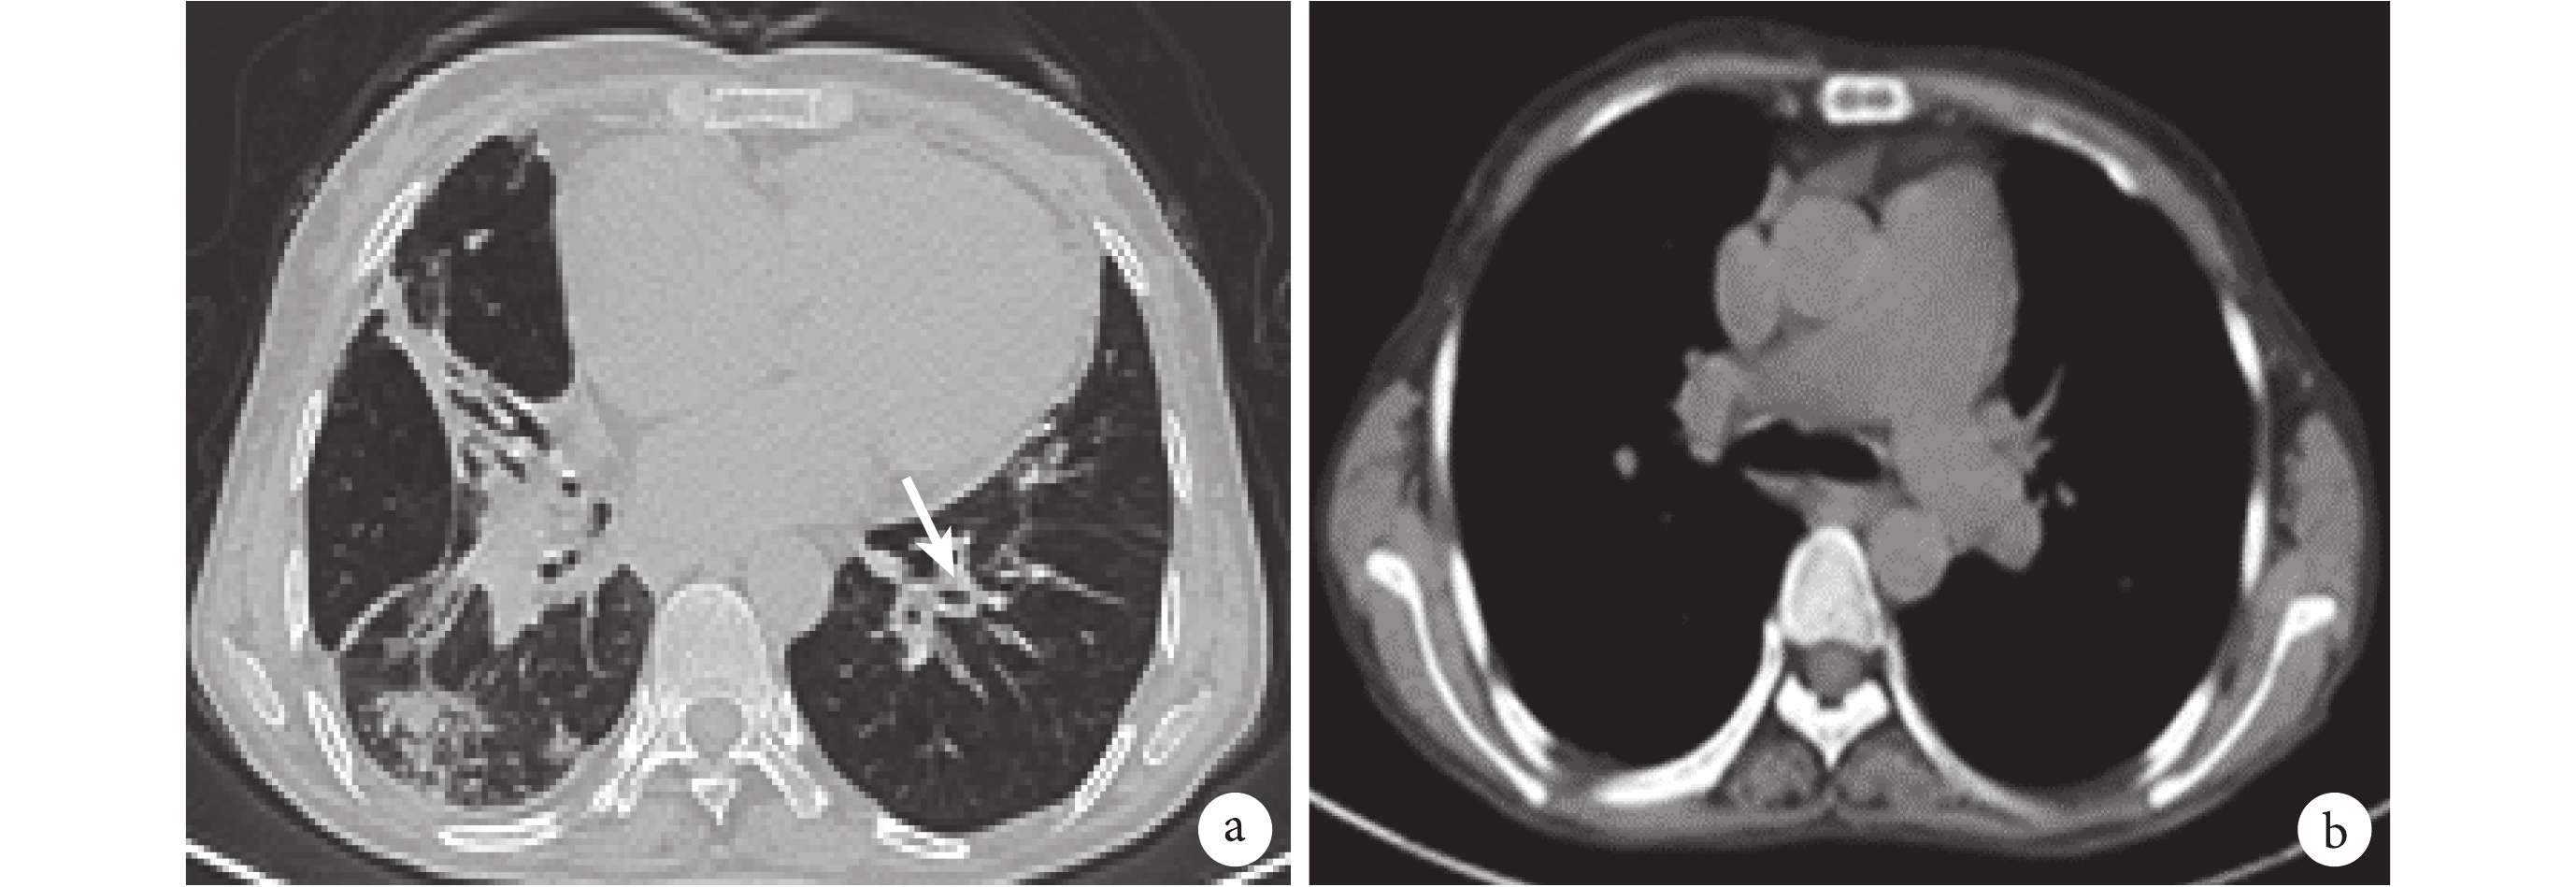

a. 肺窗,可見雙肺感染灶及支氣管擴張(白箭);b. 縱隔窗,可見肺動脈明顯增寬

患者女性,52 歲,因“反復咳嗽、咳痰 20+年,間斷雙下肢水腫 7 年,加重 3 個月”于 2018 年 1 月 5 日收入院。20+年前患者開始于受涼后出現咳嗽、咯黃色黏痰,在當地醫院給予靜脈滴注“抗生素”治療(具體不詳)后癥狀可好轉。2015 年開始上述病情發作逐漸頻繁,主要表現為咳嗽、咯黃痰和活動后呼吸困難,開始不能從事日常體力勞動,期間多次住院治療,均診斷為“肺部感染”。7 年前,患者開始出現間斷雙下肢水腫,夜間喜高枕臥位。上述癥狀頻繁發作,平均每月 2~3 次,每次均需靜脈使用抗生素后癥狀方緩解。患者日常活動嚴重受限,近 1 年幾乎無法外出活動。3 個月前,患者上述癥狀再次加重,且反復發熱,體溫波動在 38~39 ℃ 之間,來我院就診收入住院治療。患者長期生活在甘肅地區,居住地平均海拔 2 700 m。否認吸煙史、生物燃料接觸史、幼年反復呼吸道感染病史。否認家族或近親中有類似病史。入院查體:生命體征平穩。慢性病容,皮膚鞏膜無黃染,全身淺表淋巴結未捫及腫大。頸靜脈怒張。心界稍向左擴大,心律齊,各瓣膜區未聞及雜音。胸廓未見異常,雙肺聞及大量干濕啰音。腹部外形正常,全腹軟,無壓痛及反跳痛,肝肋下 2 橫指,脾腎未觸及。雙下肢輕度水腫。輔助檢查:血常規:血紅蛋白 181 g/L,白細胞 7.29×109/L,中性分葉核粒細胞百分率 78.7%。降鈣素原 0.15 ng/ml。痰培養:卡他莫拉菌生長。生化:總蛋白 51.1 g/L,球蛋白 15.0 g/L,BNP 652 pg/ml。體液免疫:IgG<0.33 g/L(參考值 8~15.5 g/L),IgA<66.70 mg/L(參考值 836~2 900 mg/L),IgM 5 740 mg/L(參考值 700~2 200 mg/L)。各項肝炎抗體、類風濕因子、自免肝抗體及所有自身免疫相關抗體檢測均陰性。B 細胞絕對計數:155 個/μl(175~322)。T 細胞絕對計數:CD4+T 246 個/μl,CD4/CD8 0.27。全血流式細胞檢測未見異常表型細胞群。EB 病毒、巨細胞病毒、結核 γ 干擾素釋放試驗、血清蛋白電泳、免疫固定電泳無異常均無明顯異常。血凝集素、Coomb 試驗(–)。胸部 CT:雙肺散在結節、斑片影,雙肺部分支氣管稍擴張,管壁增厚,部分支氣管內少許黏液栓形成;雙肺不均勻氣腫;雙肺門區軟組織影增多,腫大淋巴結?心臟增大,右心房為著;縱隔淋巴結長大;肺動脈主干及左右肺動脈干增粗;右側胸腔少量積液(圖 1)。頭部 CT:副鼻竇炎。腹部 CT:肝硬化,脾大,門脈高壓,輕度側枝循環開放,腹腔內淋巴結增多,部分增大。心臟彩超:右心稍大;肺動脈增寬,肺動脈高壓,雙室收縮功能測值正常。肺功能:第 1 秒用力呼氣容積(forced expiratory volume in one second,FEV1)和用力肺活量的比值 52.28%,FEV1占預計值百分比 34.4%,殘氣量/肺總量的比值 182.4%,肺一氧化碳彌散量 38.1 ml/(min·mm Hg)。纖維支氣管鏡:管腔未見明顯異常;肺泡灌洗液未查見惡性細胞。腹部彩超:肝臟數個實性結節,脾臟長大。肝臟超聲造影:左肝實性結節,考慮多為增生結節。胃鏡:食管靜脈曲張(中度)。骨髓穿刺涂片+活檢:增生活躍,成熟紅細胞呈厚層分布;流式細胞檢測未見明顯異常表型細胞群。結合患者反復肺部感染、支氣管擴張的病史,以及免疫相關檢查結果,擬診為 CVID 并細胞免疫缺陷、支氣管擴張、慢性肺源性心臟病、肝硬化、門脈高壓。給予抗感染、解痙、祛痰、利尿等治療,并輸注丙種球蛋白 20 g。患者癥狀好轉出院。1 個月后隨訪患者咳嗽咳痰及呼吸困難癥狀明顯改善,日常活動耐量明顯提高。囑患者院外定期輸注丙種球蛋白和胸腺肽治療。來我院常規隨訪 2 次,自訴在當地醫院注射過 3 次免疫球蛋白,反饋效果不錯,現在可以自由外出活動。